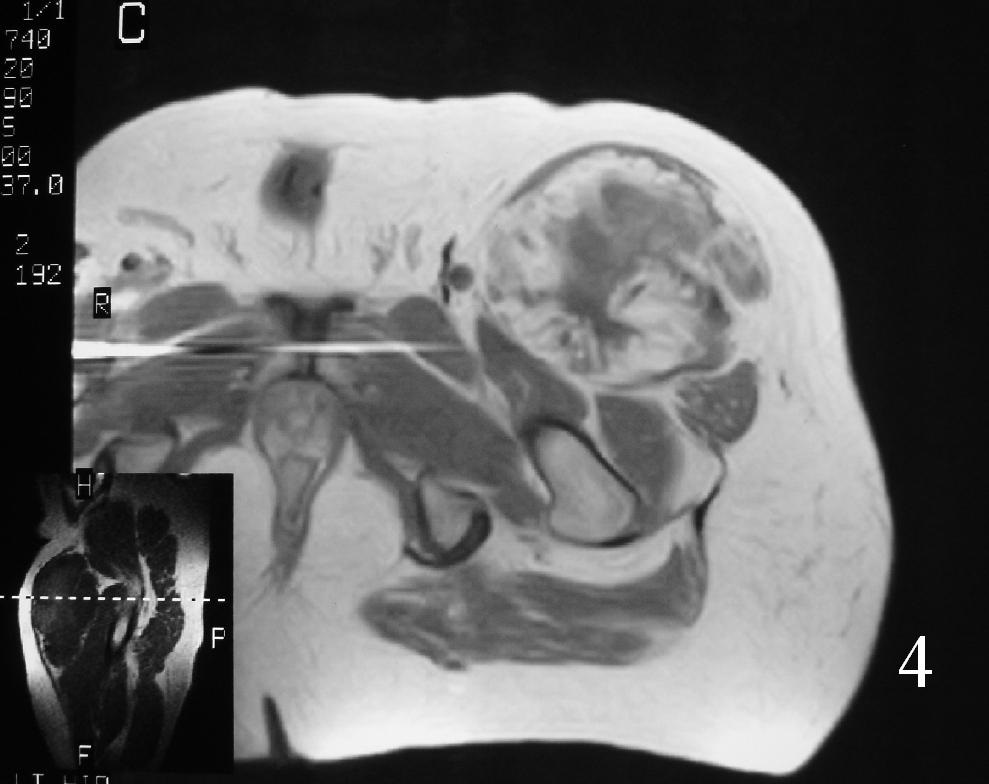

MRI (Fig. 3-7)

• Shows lobulated soft tissue mass

• Signal intensity similar to that of skeletal muscle on T1W

• Heterogenous signal intensity greater than that of fat on T2W

Fig. 4

Fig. 3-7 Axial MRI of the lower extremity shows an extraskeletal soft tissue chondrosarcoma in different sequences with and without contrast (Fig. 3, 4, 5). Sagittal MRI (Fig. 6, 7) T1 with-without contrast demonstrates enhancement of the mass